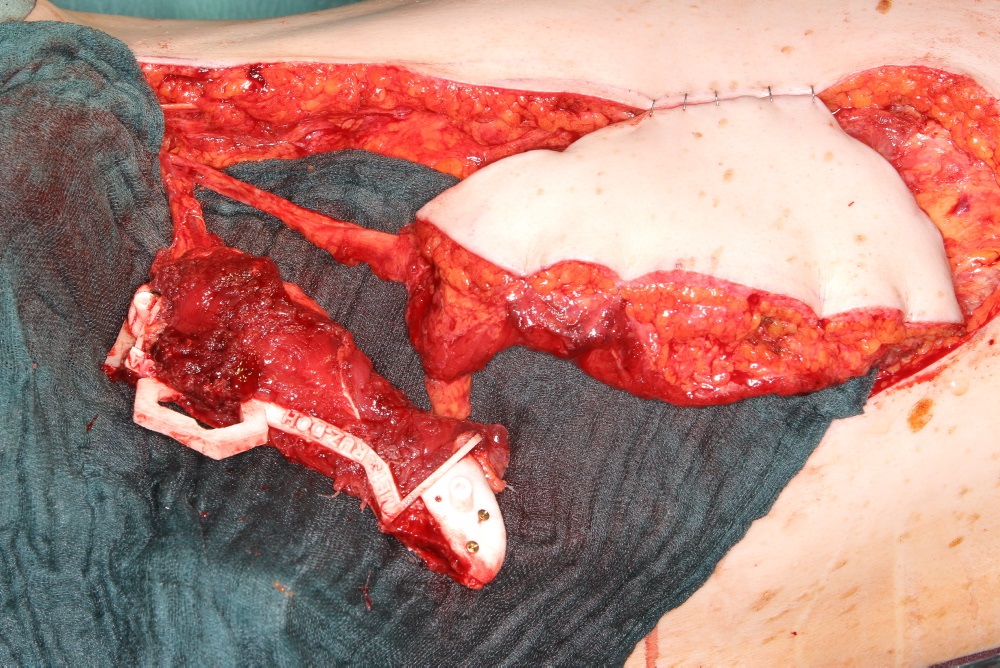

A 58-year old male oncology patient required secondary mandibular reconstruction after composite resection of the floor of the mouth, mandibular symphysis, anterior body regions of the mandible and bilateral limited neck dissection. The existing reconstruction plate bridging the anterolateral mandibular defect was widely exposed through the intraoral mucosa. The chin and lower lip was sagging due to submandibular soft tissue shrinkage and lack of bone suspension. For secondary reconstruction, a two-in-one free flap from the subscapular vascular system containing the lateral scapular border and tip in combination with a latissimus dorsi flap was selected, since severe peripheral arterial occlusive disease prohibited the use of an osteofasciocutaneous fibula free flap. VSP was used to design the bony reconstruction with three sub-segments (total length 8.1 cm) from the right (nondominant arm) lateral scapular border and tip (Fig. 4).

Scapular SLS templates or cutting guides were manufactured for secondary resection of the mandibular bone stumps, along with a set of STL models and a patient specific mandibular reconstruction plate (PSMP) (Fig. 5).

Intraoperatively, the circumflex scapular and thoracodorsal vascular pedicles were dissected to their common subscapular trunk and the angular branch supplying the scapular tip preserved (Fig. 6). In Fig. 6a, the angular vessel branch can be seen emerging from beneath the latissimus island to supply the scapular tip. An elliptical 18 cm x 7 cm myocutaneous latissimus dorsi flap was raised to provide coverage for the extensive submandibular soft tissue deficit. The in toto scapular bone flap was retrieved using the outer frame of the cutting guide (Fig. 6a). In tandem with the vertical rod and its extensions, the wedge osteotomies for segmentation were carried out on a side table (Fig. 6a and c). Prior to the flap transfer into the recipient site, the fit of the neomandibular segments was double checked within the defect of the STL model (Fig. 6d). Microanastomosis was performed end-to-end to the left maxillary artery and end-to-side to the internal jugular vein.